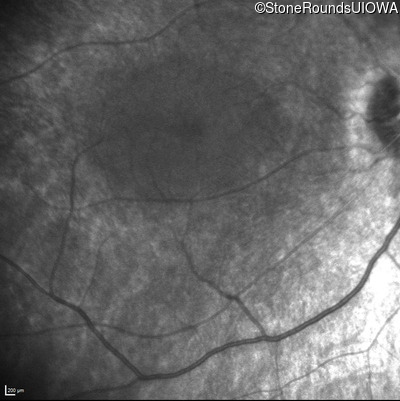

Infrared Fundus Photograph - Right - No Light Perception

Exemplar